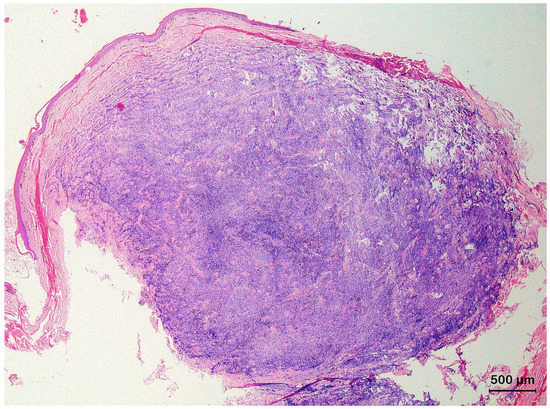

3.3. Basal Cell Carcinoma and Its Histological Variants